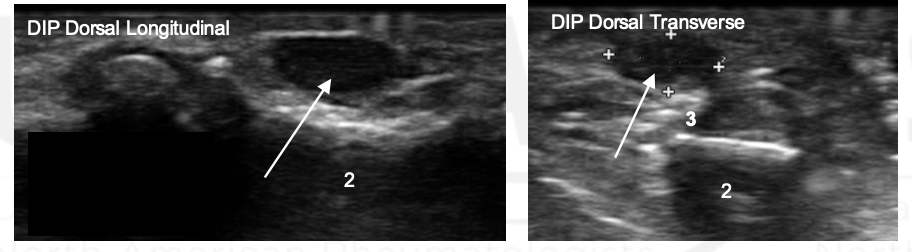

What view is this? What is the arrow?

DIP, tophus

MCP; Gout